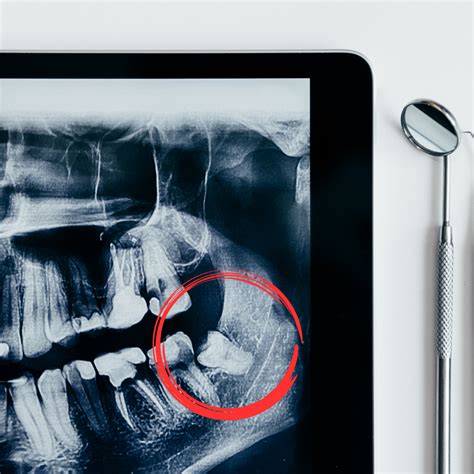

La pericoronaritis es una inflamación localizada en el tejido blando que cubre parcialmente una muela en proceso de erupción, especialmente frecuente en las muelas del juicio. Esta inflamación suele acompañarse de infección cuando el colgajo de encía, conocido como opérculo, acumula bacterias y restos alimentarios. Aunque puede afectar a cualquier molar en erupción, la mayoría de los casos de pericoronaritis se localizan en las muelas del juicio inferiores, dado que estas suelen tener más dificultades para emerger de manera completa y alineada.

La causa más común de pericoronaritis es la erupción incompleta de una muela del juicio. Cuando la pieza no termina de salir completamente, parte de la corona queda cubierta por encía. El colgajo de encía que cubre la muela forma un espacio cerrado donde no llegan ni el cepillo de dientes ni el enjuague bucal. Esta zona se convierte en un reservorio de bacterias y placa, sobre todo si no se realizan limpiezas profesionales periódicas.

La falta de espacio para la salida adecuada del molar o su erupción en una posición inclinada, provoca el contacto con el diente vecino, propiciando la entrada de restos de alimentos en el espacio creado cuando el tercer molar atraviesa la encía.

- Extracción Dental: En muchos casos, especialmente si la muela del juicio está impactada o no es funcional, se puede recomendar la extracción dental y una posterior colocación de implantes dentales. La extracción elimina la fuente de la infección y evita futuros problemas.